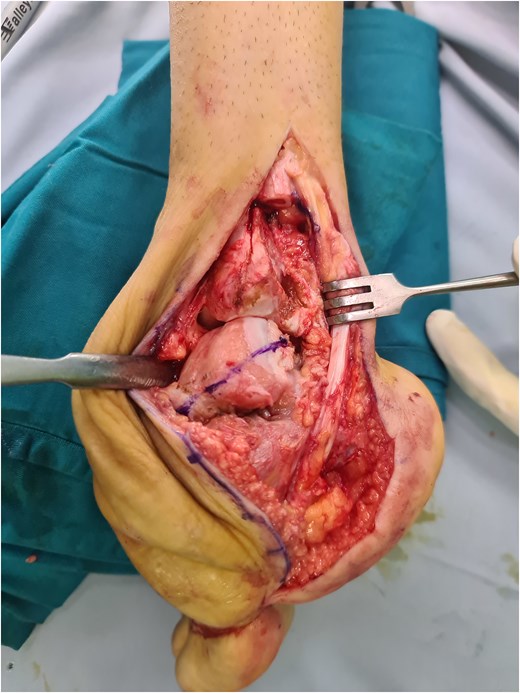

The partial talectomy method used in this case series was performed by removing a portion of the talar dome in axial plane using an oscillating saw to correct the hindfoot equinovarus deformity, mainly the equinus (Fig. 4). The bone cuts were done as much as necessary until the desired reduction was achieved. The lateral transfibular approach was selected due to its association with good exposure for deformity correction in the sagittal plane and its sufficient proximity to the articular surface. As mentioned before, bone cutting in this area will preserve the vascularization in the inferior talus or sinus tarsi, in contrast to the Lambrinudi procedure [11]. Compared with total talectomy, which results in an incongruous joint, partial talectomy is still able to facilitate proper contact between the distal tibia and cut talus. Various internal fixation methods are available to protect correction and to prevent recurrence. Generally, tibiotalocalcaneal fusion can be performed using multiple screws, plates and screws, or intramedullary nails. However, multiple screw placement would not be preferred due to poor bone stock. Gursu et al. reported the use of intramedullary nail fixation after talectomy in the management of severe rigid equinovarus deformity in adults. Intramedullary nails have a biomechanical superiority and ability to reduce incongruity between surfaces with sequential reaming [20]. Nevertheless, intramedullary nails are still not widely available worldwide, especially in developing countries, in which many similar neglected clubfoot cases can be found. Lateral plating is viable, especially when a lateral transfibular approach is used. Other than the anatomical tibiotalocalcaneal plate that is utilized in this study, various plates, such as reversed proximal humeral plates, can be applied as long as they enable sufficient screw placement [21].